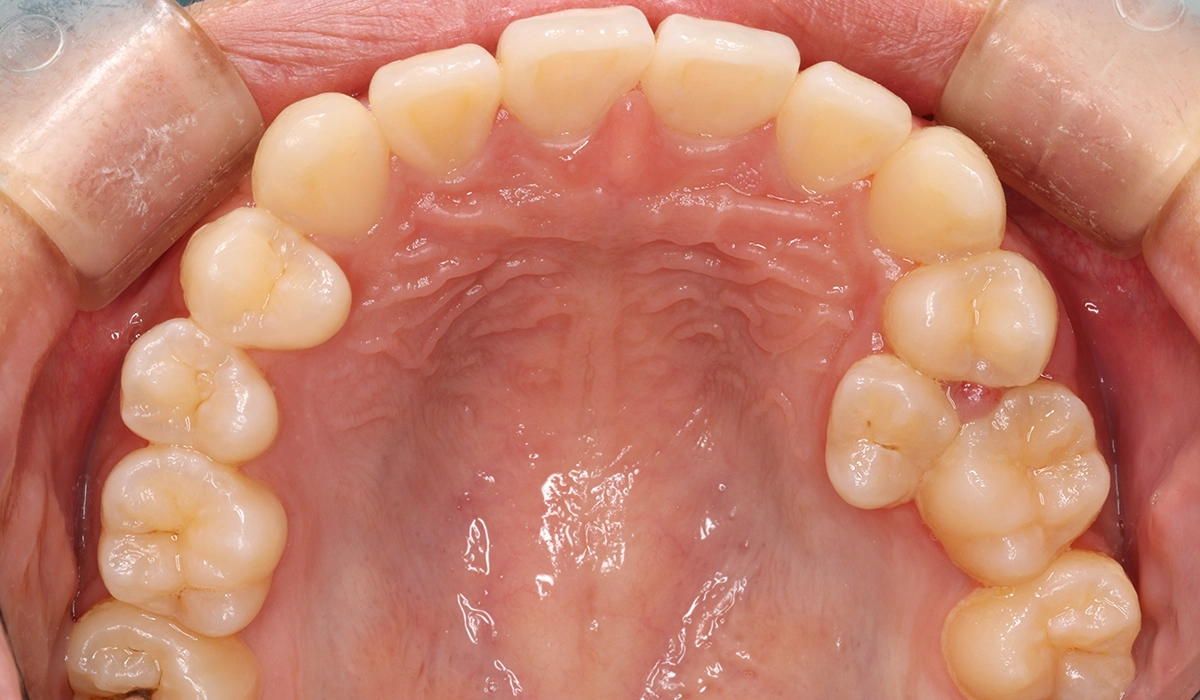

術前:上顎

術後:上顎